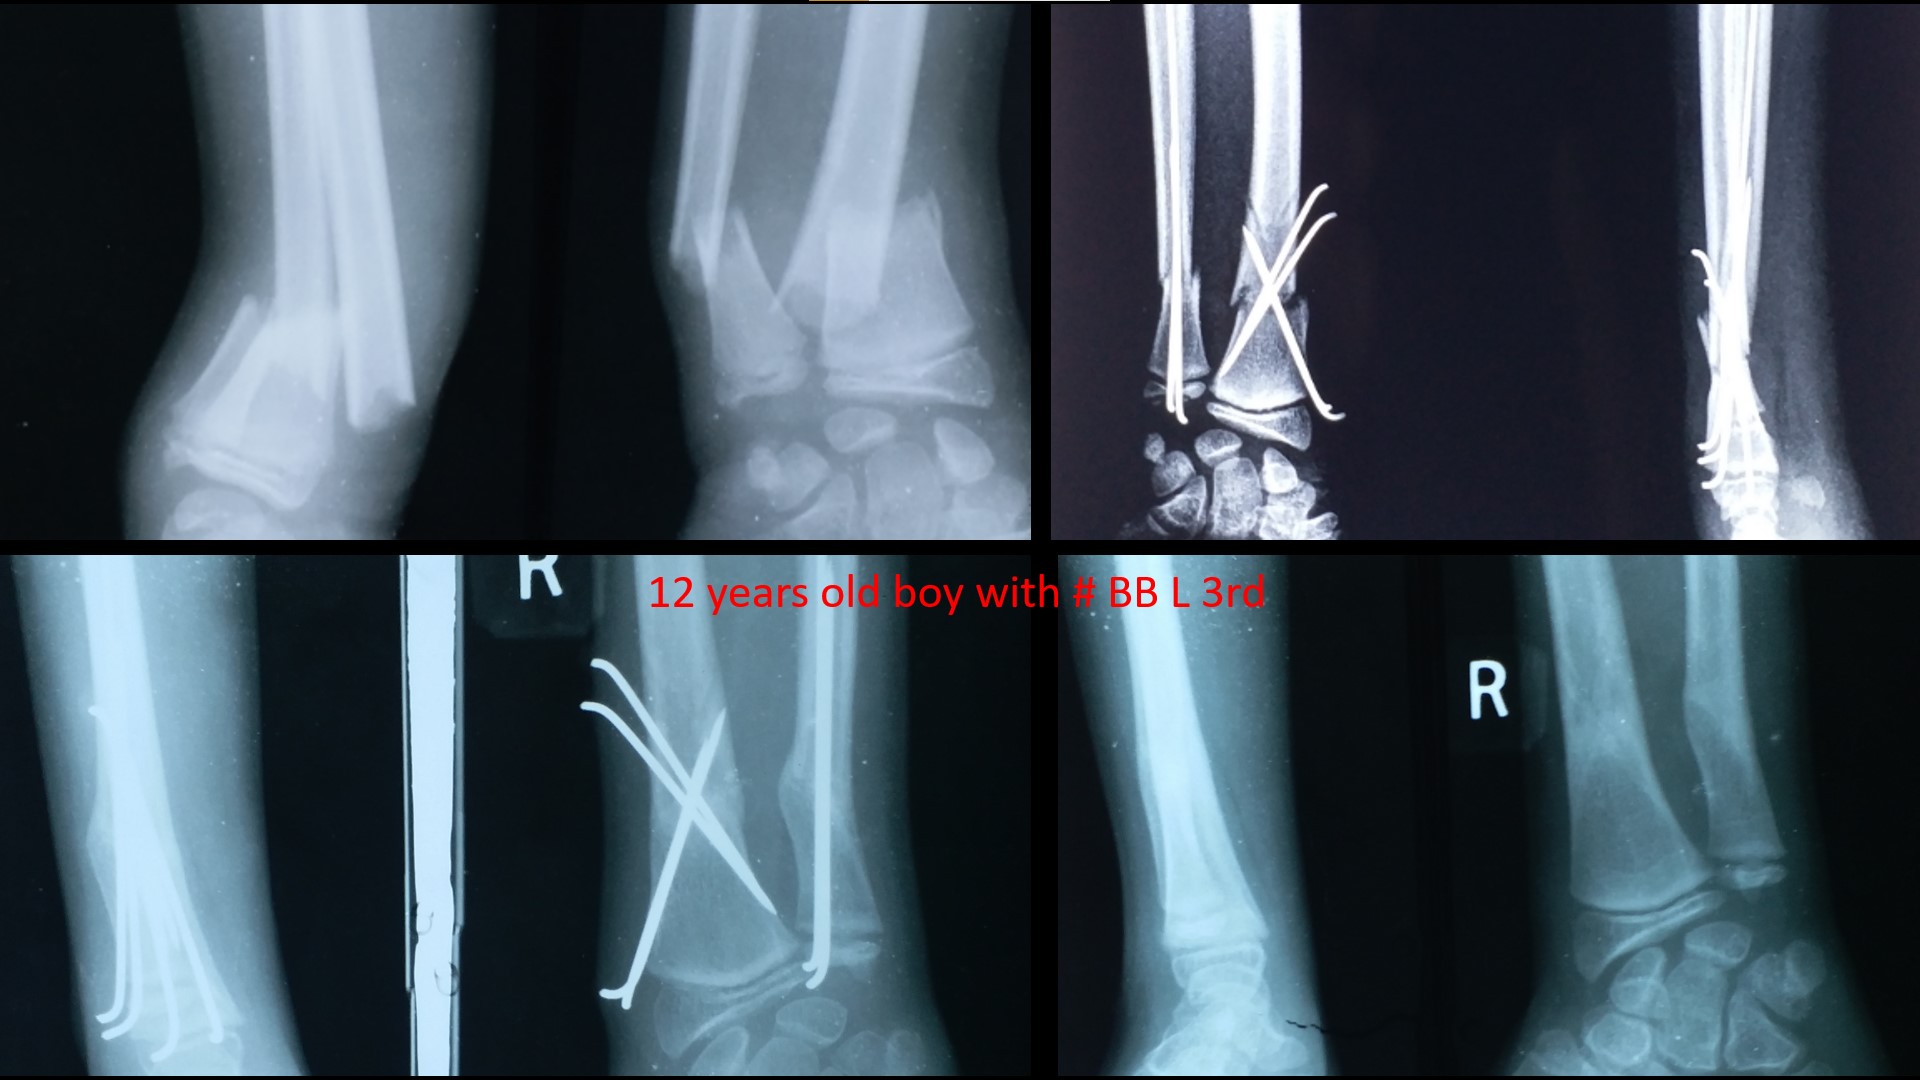

FRACTURE LOWER 3RD FOREARM